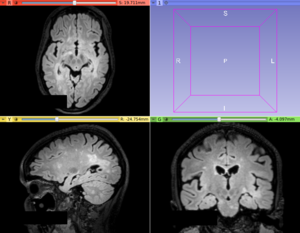

This module offers a hybrid algorithm based on the iterative contrast enhancement (ICE) and logistic classification methods for hyperintense Multiple Sclerosis lesion segmentation task.

• Use Case 1: Hyperintense Multiple Sclerosis (MS) lesions segmentation

• Hyperintense MS lesions, mainly in T2-FLAIR images, have an easy application of this lesion segmentation procedure